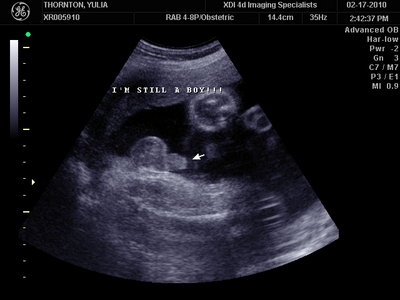

А это в 30 недель

MY BABY SONO!_20.JPG [ 94.63 КБ | Просмотров: 1169 ]

Sweetheart75 писал(а): Ну ладно, тогда и я нашего писюна покажу  Надеюсь, Джеффри на меня не обидится Вот это в 23 недели: (там оборудование переключалось из режима 3Д в обычный 2Д) Oоо, такое достоинство невозможно не заметить  А в 30 недель так вообще!